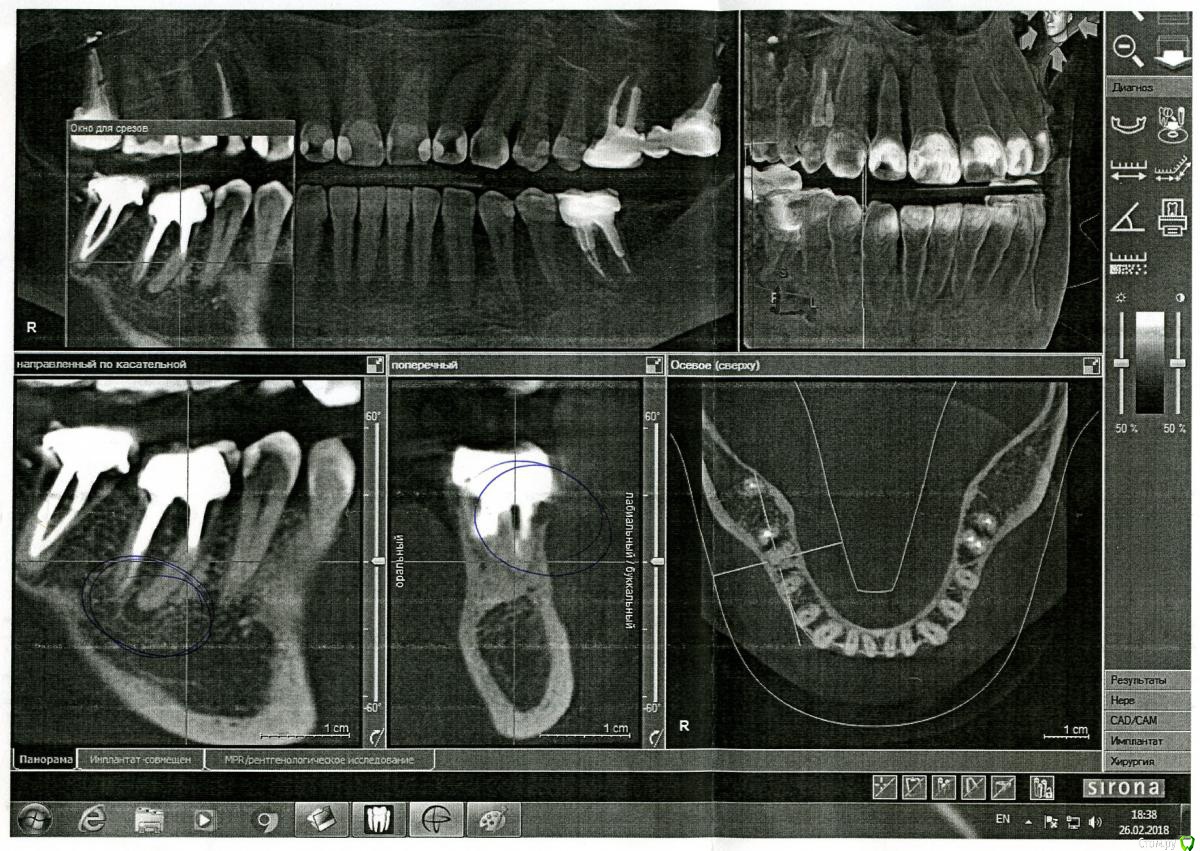

Sparrow Опубликовано 27 февраля, 2018 Поделиться Опубликовано 27 февраля, 2018 (изменено) Уважаемые специалисты.Прошу Вашего мнения относительно моей ситуации. 5 месяцев воспалена десна и сосочек между зубами.При надавливании на край десны из под десны появляются выделения белого цвета в небольшом количестве (буквально по 1 мм вдоль кромки десны). Боли нет ни в десне ни в зубе.Зуб не шатается. На зубе коронка со штифтами - ставили 14 лет назад.При обнаружении воспаления обратилась к стоматологу.Сделан снимок - на снимке ничего не обнаружено - вывод местное воспаление. К такому же выводу пришли впоследствии еще три специалиста - снимок делали еще 2 раза - ничего не находили . За это время (5 месяцев) было сделано 2 чистки - 1 локально - ультразвук под десной - сильно кровоточило и сосочек на следующий день "сдулся" до нормального размера,но выделения остались и через время десна снова увеличилась.Вторая чистка - полностью полость рта. Состояние десны осталось прежним.Выделения есть.Применила уже все возможные варианты полосканий - хлоргексидин-мирамистин-ромашка-сода-парадонтакс-стоматофит - полностью успокоить десну не удается. Обратилась снова к стоматологу. Сделали КТ. Киста на корне зуба и кариес корня под десной. Зуб удалять однозначно или есть еще минимальная возможность его спасти? (мне крайне неудобно показывать вам этот цветной налет на зубах - но это то,что вышло от применения супермягкой щетки Парадонтакс и ополаскивателя Парадонтакс-Экстра за полтора месяца после последней гигиенической чистки) Изменено 27 февраля, 2018 пользователем Sparrow Ссылка на комментарий